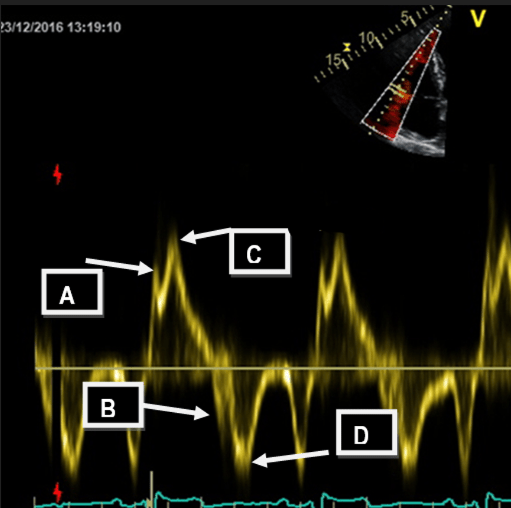

This is the point AND the name of the measuremnt that is measured for right sided Tissue Doppler Imaging (TDI), a measurement of the maximum velocity of the tricuspid lateral annulus during systole.

What is S' (S prime) and pont C?